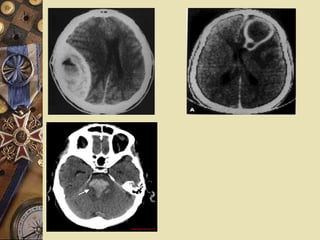

 Coma with focal signs

 • Vascular : infarction (Ischaemia ,Embolic) ,

Haemorrhage (EDH,SDH,SAH)

Investigations

 • Metabolic , toxicology screen

 • CT scan or MRI if possible, especially in

coma with meningism or focal signs.